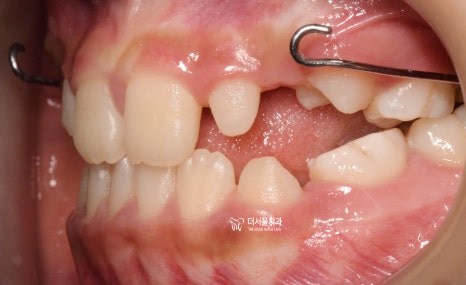

그렇게, 페이스 마스크 및 악궁확장장치를

끼니 윗니가 아랫니가 덮는 overjet 이

형성 되어있는 것을 볼 수 있네요.

"상황이 더 나빠졌네요."